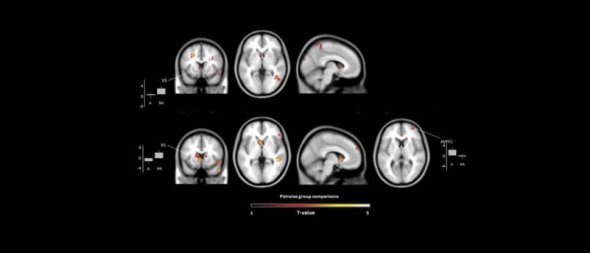

Команда вчених спостерігала за виробленням гормону радості дофаміну в мозку 24 учасників. 12 з них були пов'язані зі сферою мистецтва - актори, скульптори, музиканти, фотографи, художники. До іншої групи увійшли страхові агенти, стоматологи, адміністратори, інженери - представники "нетворчих професій".

Процеси в мозку сканували за допомогою апарату МРТ.

Мозок творчих людей демонстрував підвищену активність, коли було потрібно знайти потрібний колір без перспективи отримати за це гроші.

"Дійсно, існує зв'язок між ставленням художників до грошей і активністю деяких областей їхнього мозку, - каже німецька нейробіолог Роберто Гойя-Малдонадо з Медичного центру в Геттінгені. - В цілому, результати вказують на наявність у мозку художників окремих нейронних ознак, що пригнічують їхню реакцію на важливість грошової винагороди".